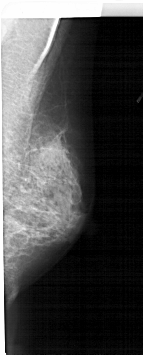

A_1609_1.LEFT_CC

LEFT_CC LINES 4006 PIXELS_PER_LINE 1861 BITS_PER_PIXEL 12 RESOLUTION 43.5 OVERLAY